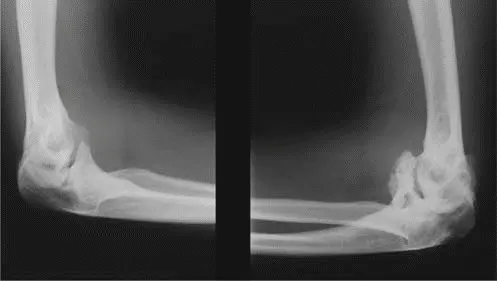

تُظهر الأشعة السينية علامات مميزة لخلل التنسج المشاشي المتعدد والتهاب المفاصل الشديد. في حالة المريض، كشفت الأشعة السينية عن:

- رأس فخذ كبير ومسطح (Coxa Magna and Coxa Plana): رؤوس الفخذين كانت متضخمة بشكل ملحوظ ولكنها مسطحة للغاية، مع تعظم غير منتظم.

- عنق فخذ قصير وعريض: وهو سمة مميزة للحالة.

- خلل تنسج الحُق (Acetabular Dysplasia): تجاويف الحُق كانت ضحلة، مع تغيرات تصلبية وتكيسات تحت الغضروف.

- تضيق المسافة المفصلية: اختفاء كامل للمسافة المفصلية العلوية والأمامية، مما يشير إلى التهاب مفاصل حاد.

- نتوءات عظمية (Osteophytes): تشكل نتوءات عظمية واسعة حول رؤوس الفخذين وحواف الحُق.

- تصلب تحت الغضروف (Subchondral Sclerosis): تصلب منتشر تحت الغضروف يعكس العملية التنكسية المزمنة.

تُظهر هذه الصورة بالأشعة السينية الأمامية للحوض النتائج المميزة لالتهاب مفصل الورك الثنائي المتقدم في سياق خلل التنسج المشاشي المتعدد، وتحديداً رؤوس الفخذ غير المنتظمة والمسطحة (coxa plana) وأعناق الفخذ المتسعة (coxa magna)، بالإضافة إلى تضيق شديد في المساحة المفصلية وإعادة تشكيل الحُق.